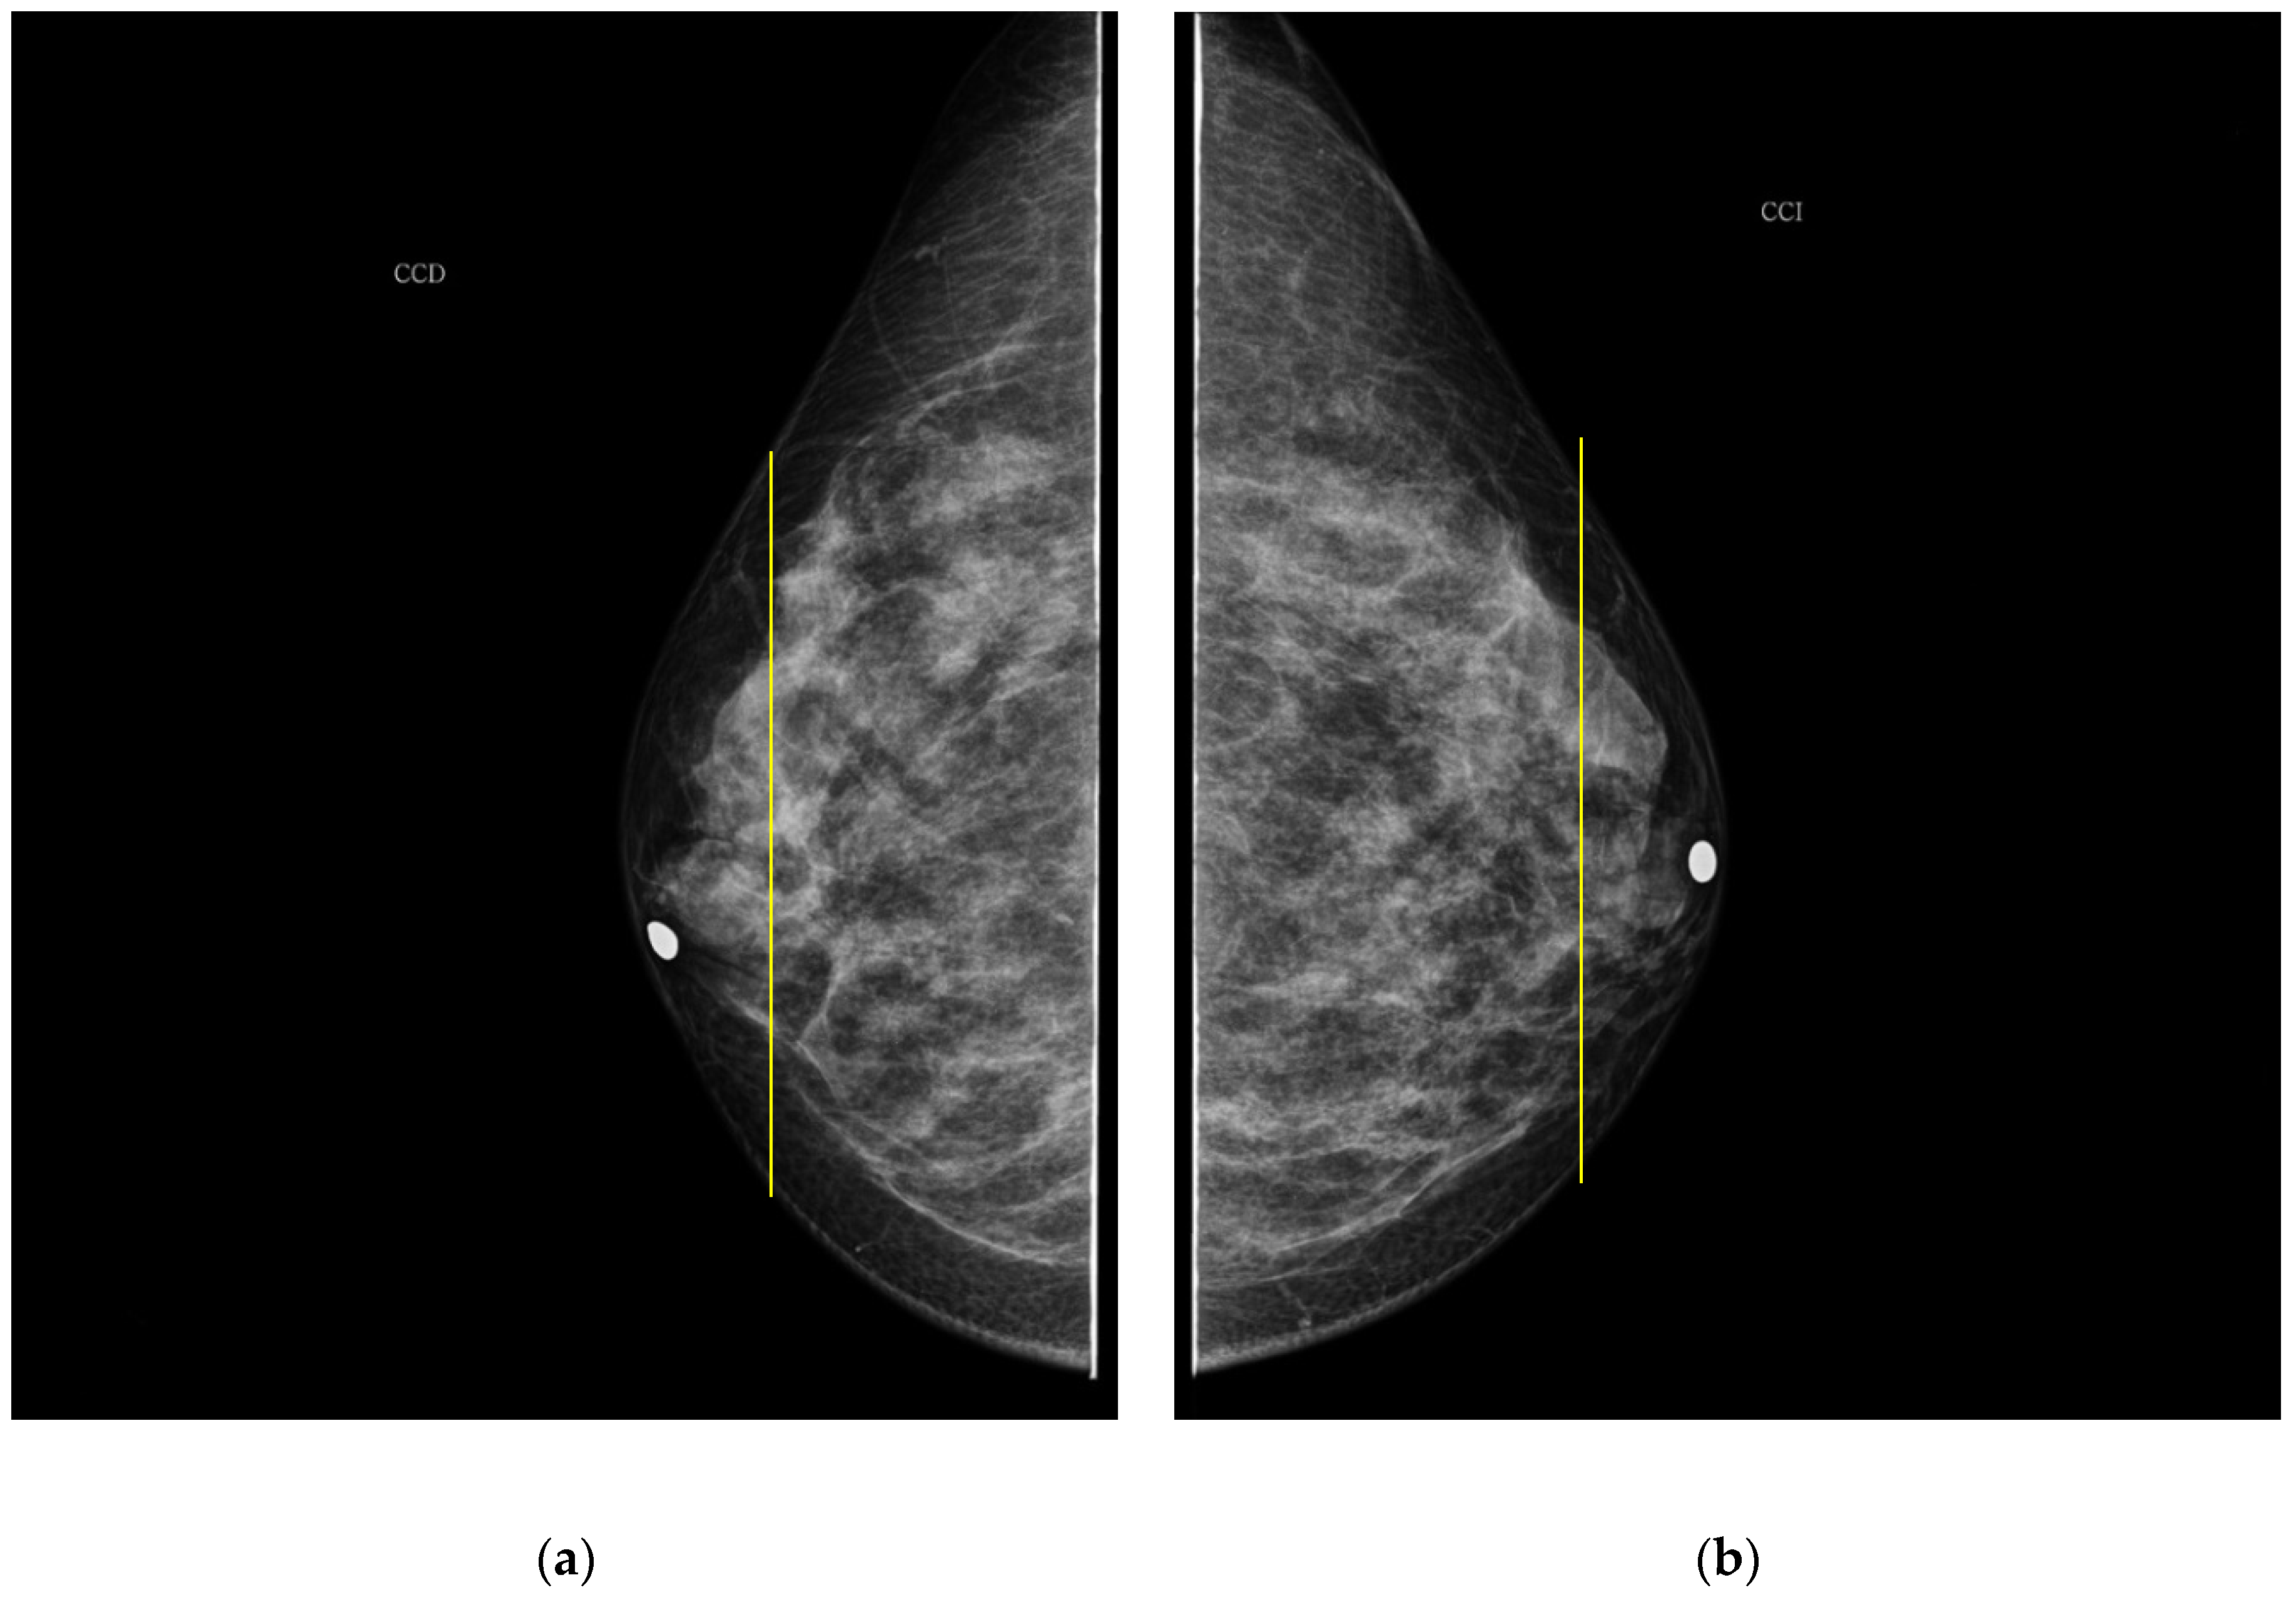

The PBD evaluated by the specialist for participant 1 is BI-RADS c for both breasts, and the outcome for the described clustering method is BI-RADS d and c for right and left breast, respectively. The CC mammography images for both breasts are presented in Figure 7, where the respective electrode ring positions are illustrated by the vertical yellow line. As it can be observed, there is a greater breast tissue in the plane covering the vertical yellow line of right breast than that corresponding to the left one. That is the reason why the resulting sectional PBD of right breast is greater than the left breast.

Figure 7. CC mammogram images of participant 1 and relative electrode ring position (yellow vertical line): (a) right breast; (b) left breast.